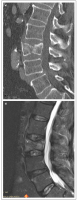

Möglichkeiten der direkten Zementinjektionstechnik bei Wirbelkörperfrakturen - Drei Fallbeschreibungen der Radiofrequenz-Kyphoplastie (RFK) mit ultrahochvikösem Knochenzement

Journal für Mineralstoffwechsel & Muskuloskelettale Erkrankungen 2012; 19 (3): 124-130 Volltext (PDF) Summary Praxisrelevanz Abbildungen